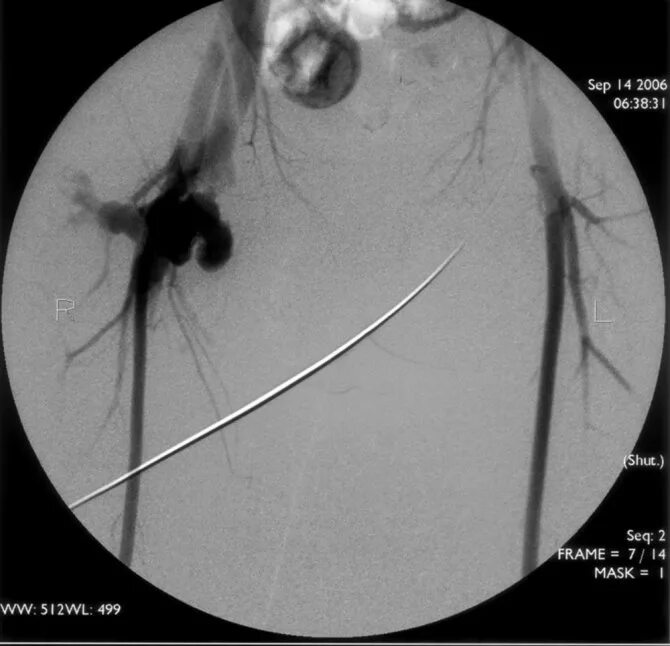

Гематома после пункции лучевой артерии. пульсирующая гематома и ложная аневризма. ложная аневризма бедренной артерии. псевдоаневризма, пульсирующая гематома.

Пульсирующие гематомы. пульсирующая гематома и ложная аневризма. пульсирующая гематома бедренной артерии. ложная травматическая аневризма.

Пульсирующие гематомы. пульсирующая гематома бедренной артерии. постпункционная ложная аневризма. пульсирующая гематома и ложная аневризма.

Пульсирующая гематома бедренной артерии. постпункционные гематомы. пульсирующая гематома и ложная аневризма. постпункционная пульсирующая гематома.

Чрескожное вмешательство на коронарных артериях. тромбоз подвздошной артерии узи. пульсирующая гематома бедренной артерии на узи. пульсирующая гематома бедренной артерии после стентирования.